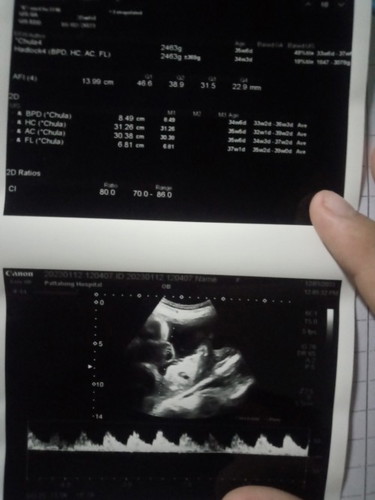

ตอนนี้36สัปดาห์5วัน ป้าหมอว่าน้ำหนักน้อง2490กรัมตามเกณฑ์ดี เเต่สำหรับแม่ว่าน้อยไปค่ะ ทานอะไรน้ำหนักลงน้องดีค่ะ❤️👶 #ท้องเเรกค่ะ#กำหนด4กุมภา66ค่ะ##ขอบคุณล่วงหน้านะคะ ☺️💖